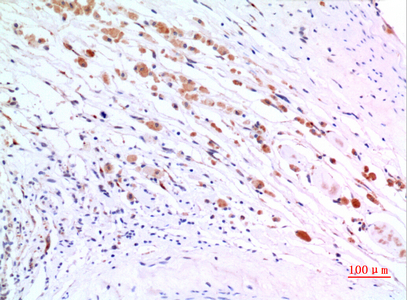

Immunohistochemistry analysis of paraffin-embedded Human brain using ZNF307 antibody. High-pressure and temperature Sodium Citrate pH 6.0 was used for antigen retrieval. |